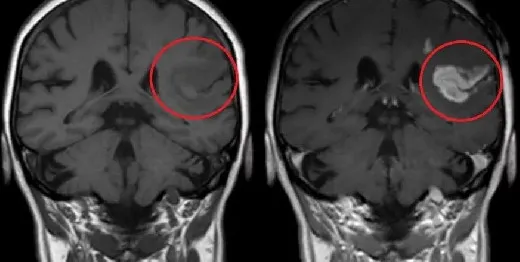

Что конкретно показывает такой вид томографии? В первую очередь — патологические очаги, которые в обычном МРТ выглядят как нечто неясное или вообще не визуализируются. Контраст «подсвечивает» новообразования, помогает отличить рубцовую ткань от активного воспаления, проследить за кровоснабжением органа или опухоли. Особенно ценна эта методика в нейровизуализации: при подозрении на опухоль головного мозга, менингиому, аденому гипофиза или метастазы — без контраста порой невозможно поставить точный диагноз. То же касается и позвоночника: при воспалительных заболеваниях, таких как спондилит, или при рецидиве после операции на межпозвоночной грыже.

В онкологии контрастное мрт — настоящая находка. Оно позволяет не только обнаружить опухоль, но и оценить её структуру, границы, степень прорастания в соседние ткани, а также эффективность проводимой химиотерапии или лучевой терапии. При этом процедура остаётся абсолютно безболезненной и не требует особой подготовки — разве что сдать анализ на креатинин, чтобы убедиться, что почки справляются с выведением контраста. Противопоказания минимальны: в основном это тяжёлая почечная недостаточность или индивидуальная непереносимость компонентов препарата.